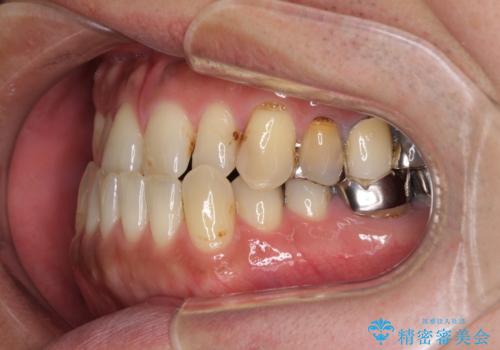

- 咬み合わせの悪さを気にして来院された患者様です。

来院当初は、奥歯の銀歯が問題で咬み合わせが悪いと思っていらっしゃいましたが、前歯の反対咬合を改善することが最優先とご説明し、矯正治療を行うこととしました。

奥歯には抜歯が必要な歯があったため、事前に抜歯を行い、その後ワイヤー装置にて治療を開始しました。